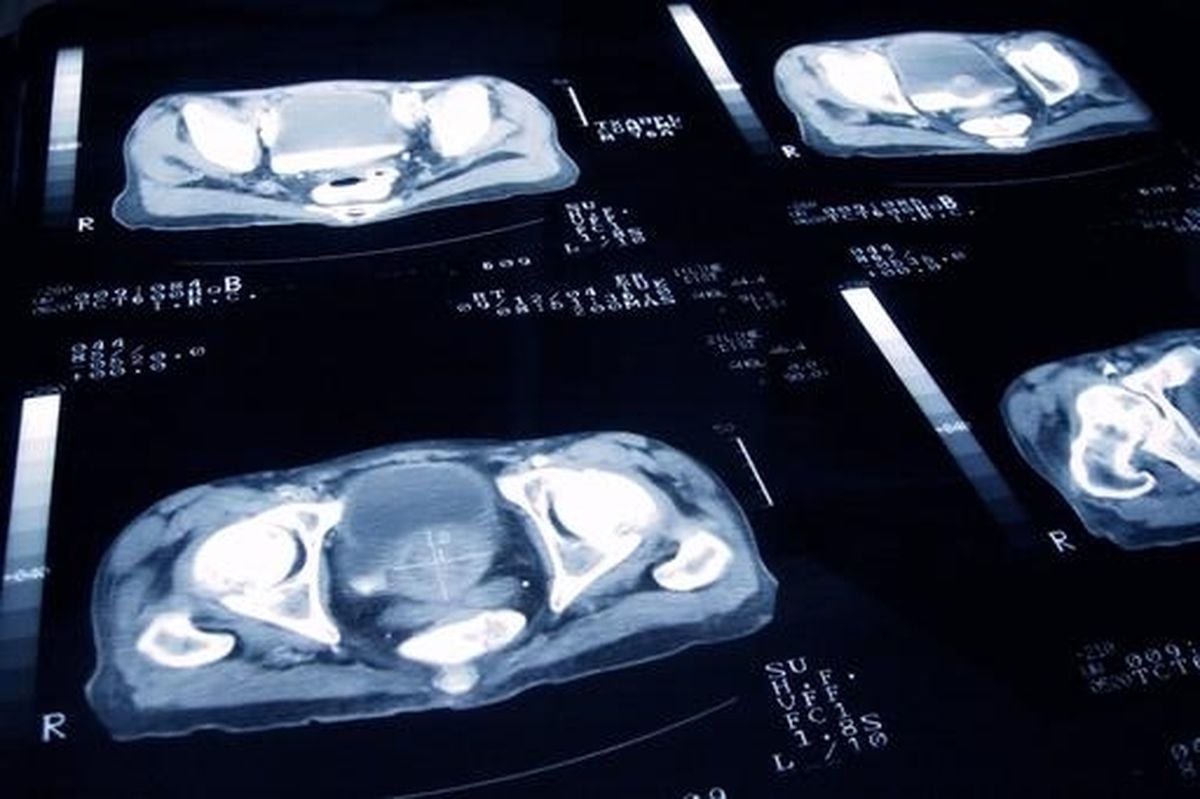

The scale of the trial is unprecedented. In its first phase, 16,000 men aged between 50 and 74—or as young as 45 for certain high-risk groups, including Black men—will be recruited. The study is rigorously comparing several innovative screening techniques against the NHS’s existing approaches, which typically rely on blood tests for prostate-specific antigen (PSA) and biopsies. Now, however, the arsenal has been expanded: genetic saliva tests, rapid MRI scans (dubbed "prostagrams"), and advanced combinations of these methods are all on the table.

Professor Hashim Ahmed, chairman of urology at Imperial College Healthcare NHS Trust and chief investigator of the trial, captured the sense of urgency and hope: “Transform is truly game-changing… the start of recruitment today marks a pivotal step towards getting the results men urgently need to make prostate cancer diagnosis safe and more effective so that we can unlock the potential of prostate cancer screening in the UK.” He emphasized the need for better screening, stating, “Combining our world-class team of UK researchers, the latest screening techniques like fast MRI scans, PSA blood tests and genetic tests, we can find the best way to screen men for prostate cancer – minimising late diagnosis, saving more lives and doing so with fewer harms.”